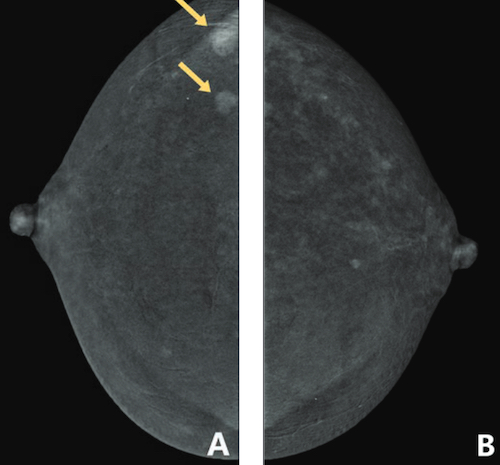

Un rehaussement tissulaire constaté sur les mammographies avec injection de produit de contraste

Dans cette étude, ont participé 207 patientes (âge médian, 46 ans) qui ont fait l’objet d’une mammographie avec injection de produit de contraste entre avril 2020 et septembre 2021. Deux radiologues ont indépendamment évalué le degré de rehaussement sur cet examen (minimal, léger, modéré ou marqué). En examinant les dossiers patients informatisés pour les facteurs cliniques, la paire de radiologues est parvenue à un consensus sur la densité mammaire via la mammographie de contraste.

Ils ont conclu que le rehaussement précoce n’était pas associé à l'âge, aux antécédents de cancer du sein, à la chimiothérapie ou à la radiothérapie, ainsi qu'au statut périménopause et postménopause. À l’inverse, il était positivement associé à des seins denses et à un statut préménopause avec des cycles irréguliers.